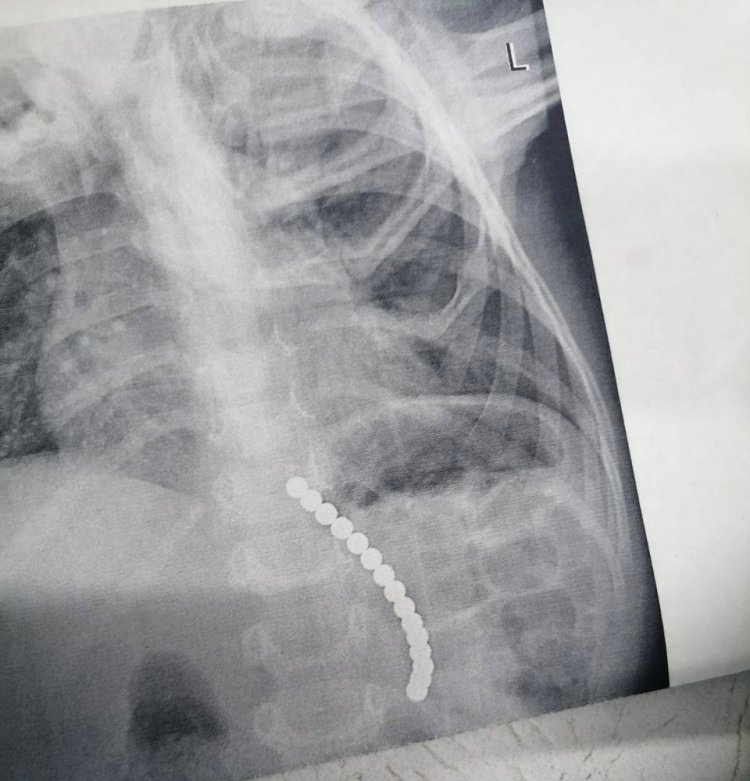

Сегодня у дежурной смены эндоскопистов Центра детской хирургии Оренбурга была непростая ночь. Врачам пришлось доставать крупные бусины из желудка 3-летнего ребёнка. По данным Минздрава, хирурги извлекли 15 магнитов. Сообщается, что маленького пациента доставили из Сорочинска. За оперативную работу в Министерстве поблагодарили врача ОДКБ Милюкову и медсестру Ушакову.

Фото: Министерство здравоохранения Оренбургской области.